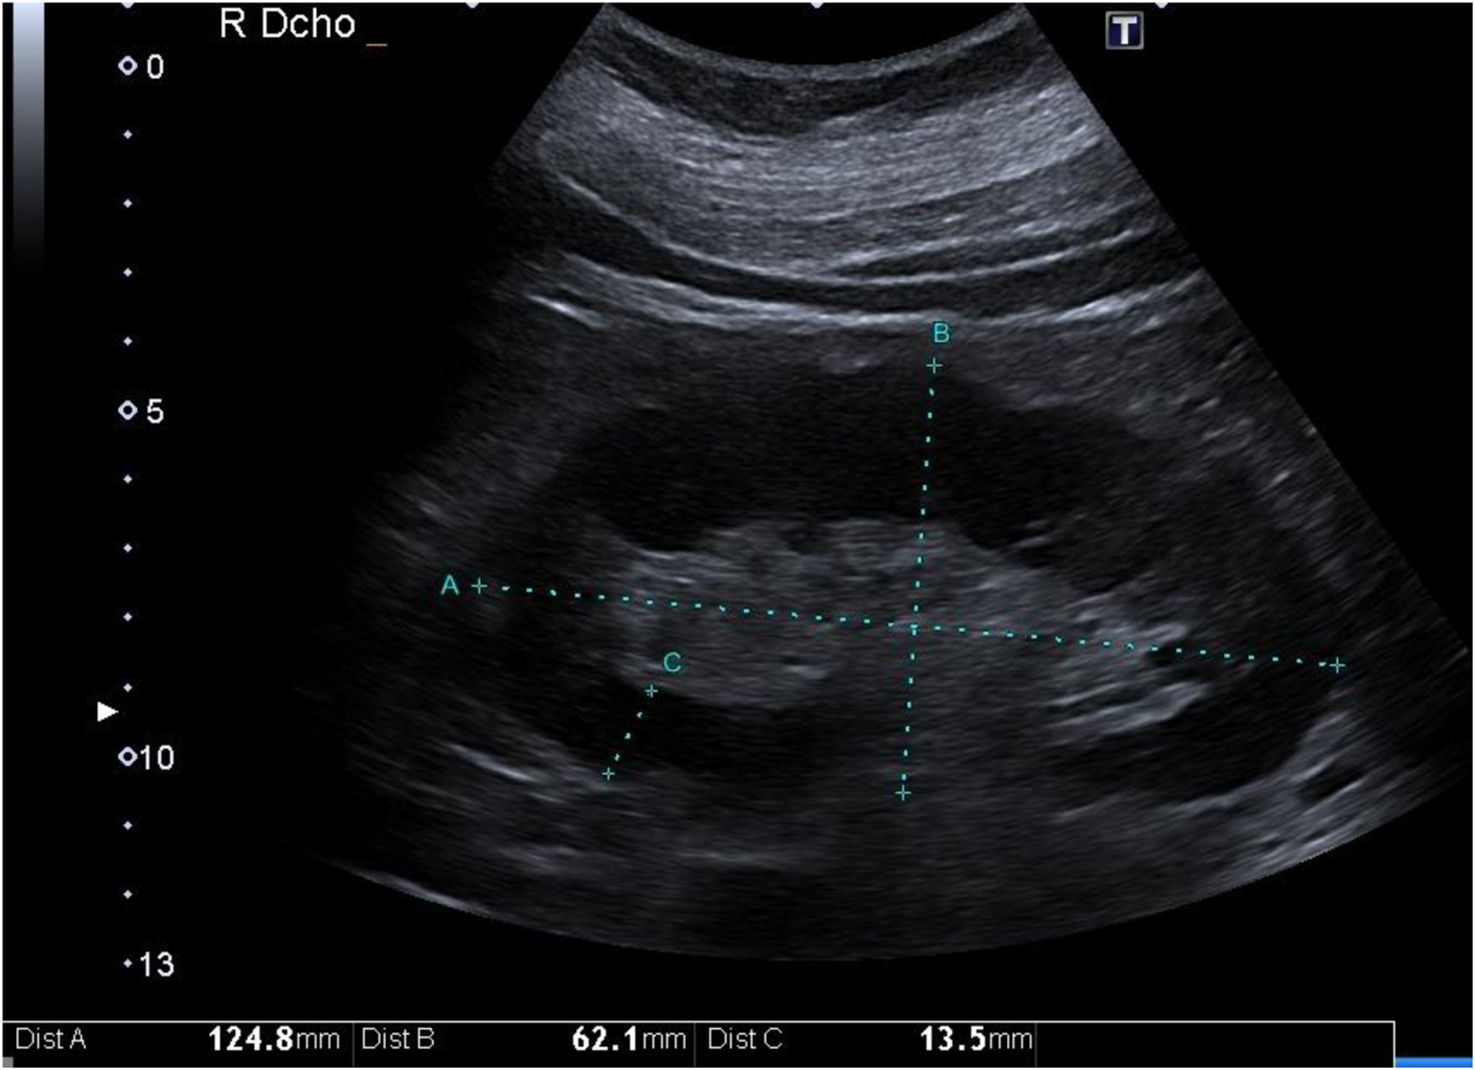

Parenchymal thickness is correlated with the degree of CKD, and the strength of this correlation is significantly increased when the thickness is corrected for body height.1 It is also inversely associated with the degree of tubular atrophy. However, this is not the case for cortical thickness11 (Fig. 1).

Figure 1.

Low-frequency convex probe (3.5–5 mHz) placed between the midaxillary line and the anterior axillary line. Longitudinal plane of the right kidney. (A) Longitudinal axis, (B) transverse axis, (C) parenchymal thickness.